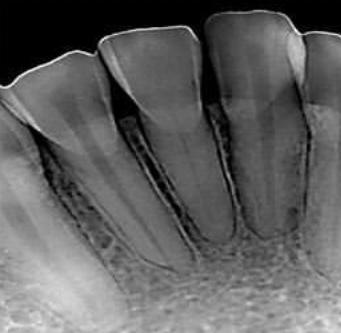

La Endodoncia o Tratamiento de Canal es el mejor procedimiento que puede realizarse en una clínica dental, ya que tiene como finalidad preservar las piezas dentales dañadas, causadas por lesiones inflamatorias en el interior del diente o pulpa dental, evitando así su pérdida. Para ello, se extrae la pulpa dental  (se encuentra en el interior del diente y contiene vasos sanguíneos, nervios y tejido conectivo). y la cavidad resultante, se rellena y sella con material totalmente biocompatible con los tejidos del diente.